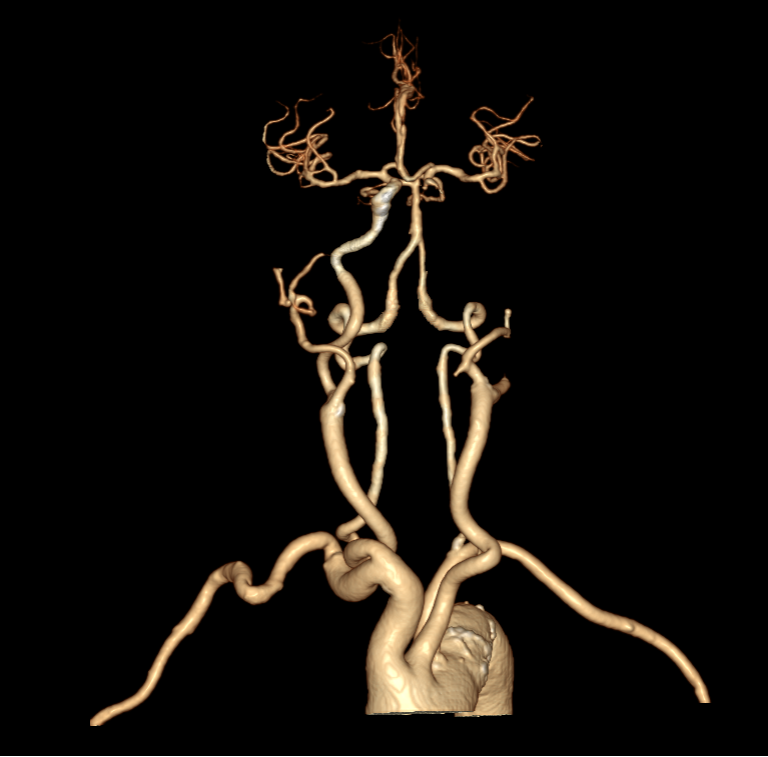

进一步的血管检查(CTA+CTP)发现了更严重的问题:王奶奶的左侧颈内动脉完全闭塞——这是脑梗中最凶险的类型之一,意味着大脑主要供血通道被切断,随时可能危及生命

头颈部CTA